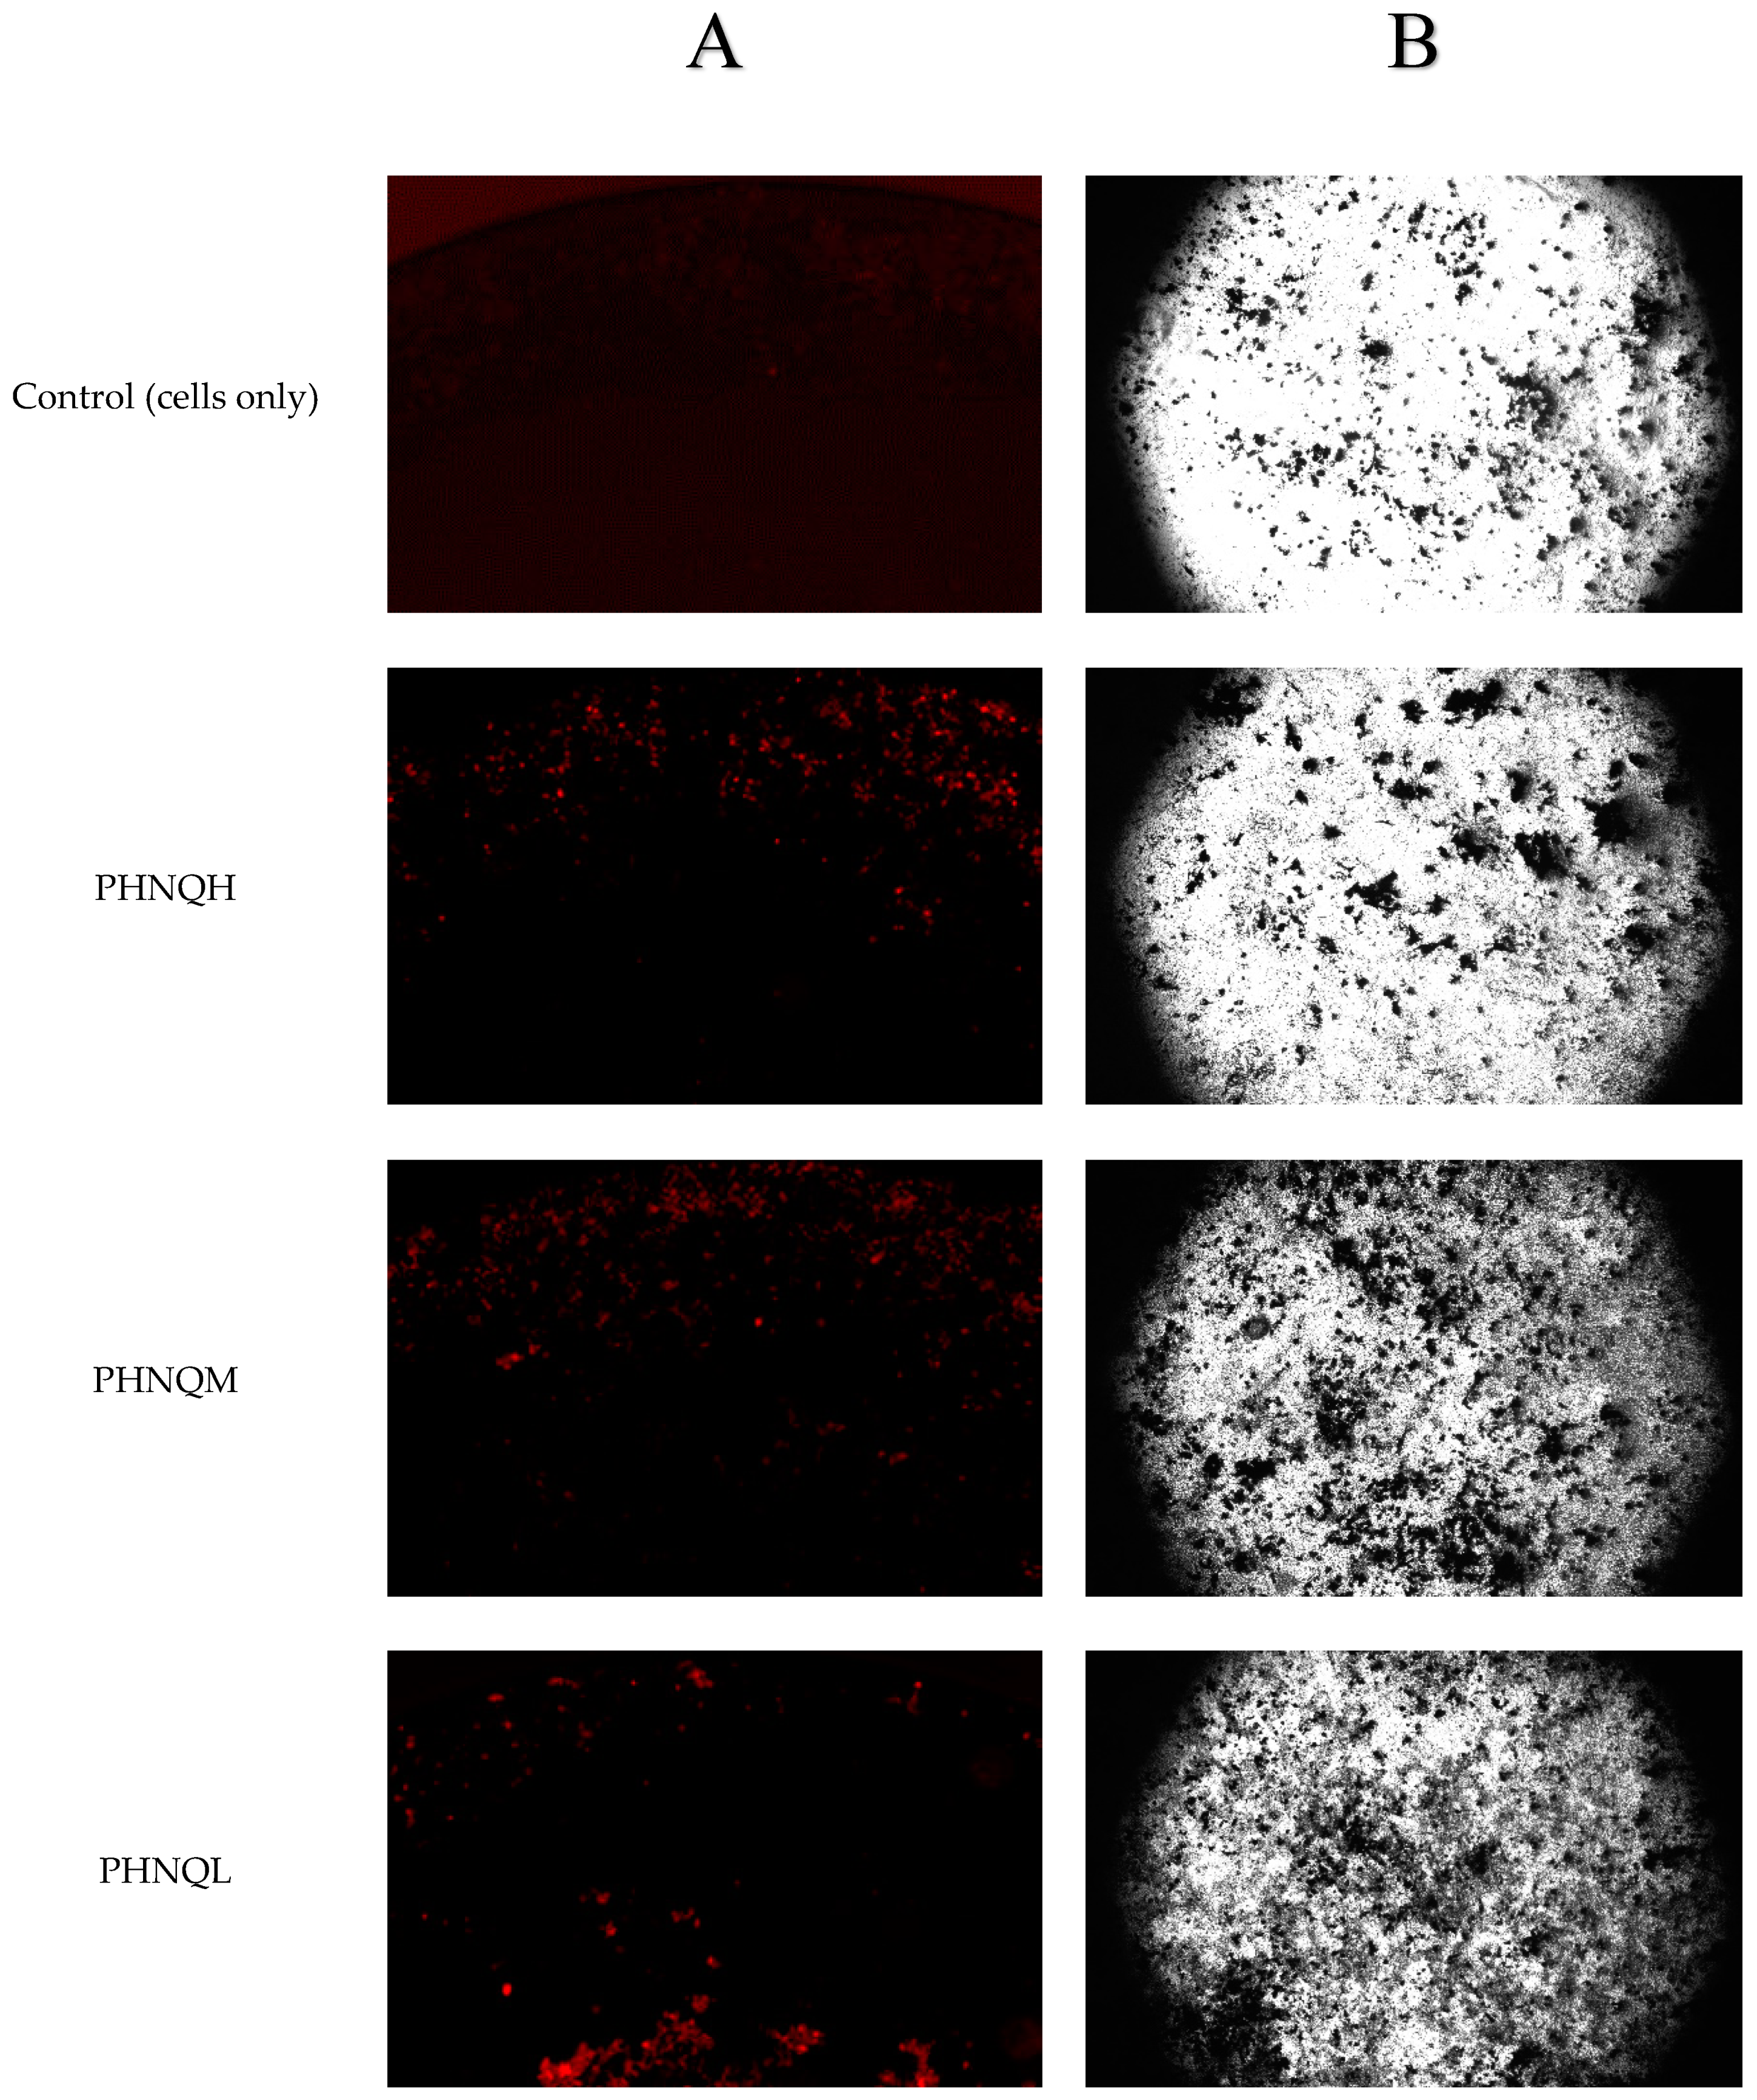

2.6. Effect of PHNQ Extract and Echinochrome A on Mineralization of Saos-2 Cells

4.6. Determination of Mineralized Nodule Formation by Xylenol Orange Staining

4.7. Determination of Mineralized Nodule Formation by von Kossa Staining